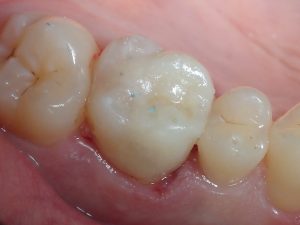

INLAY réalisé en CFAO (caméra à empreinte optique)

Inlay collé sous isolation

la dent « biogreffée » parait toute neuve!!